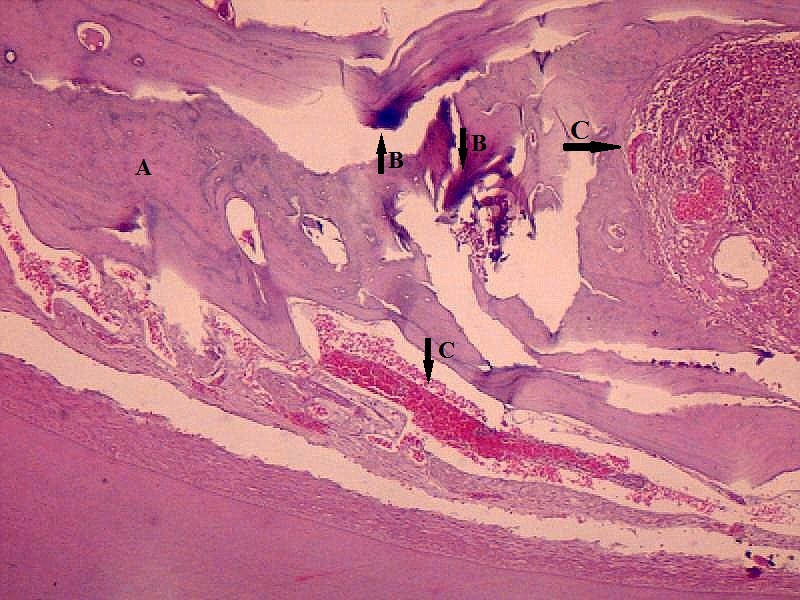

Methods: A total of 45 wistar rats were taken and divided into 3 groups (15 each). Group A, B & C rats were daily given distilled water alone (control), distilled water containing 10 mg/l (low dose) and 20 mg/l (high dose) of Sodium Arsenite (NaAsO2) respectively for 14 weeks. Animals were sacrificed, mandibles and maxillae were dissected and submitted for microscopic assessment of pathological changes.

Results: Histological changes including focal loss of osteoblastic activity and congestion of matrix vessels were observed in mandibles and maxillae of all experimental animals in both groups. Comparing maxillae in group B vs group C, focally hypocellular bone matrix (67% vs 78%), hyperplastic bony trabeculae (56% vs 22%), sequestra of acellular necrotic bone (33% vs 44%) and calcifications (56% vs 33%) were observed. Comparative histology in mandibles revealed only hypocellular matrix (89% vs 100%) and hyperplastic bony trabeculae (67% vs 78%). Comparative bone marrow changes including hypocellularity, haemorrhage, fatty degeneration and fibroreticulosis were observed as (67% vs 89%), (56% vs 89%), (33% vs 56), (22% vs 33%) respectively in maxillae and (100% vs 89%), (100% each), (33% vs 89%) and (22% vs 78%) respectively for mandibles. In comparison to group A, bone lesions were significantly associated with group B and C (P<0.05).

Conclusions: Inorganic arsenic induces degeneration of marrow and prenecrotic changes in jaw bones which calls for stringent measures aimed at its environmental decontamination and quality control in formulating HMPs.